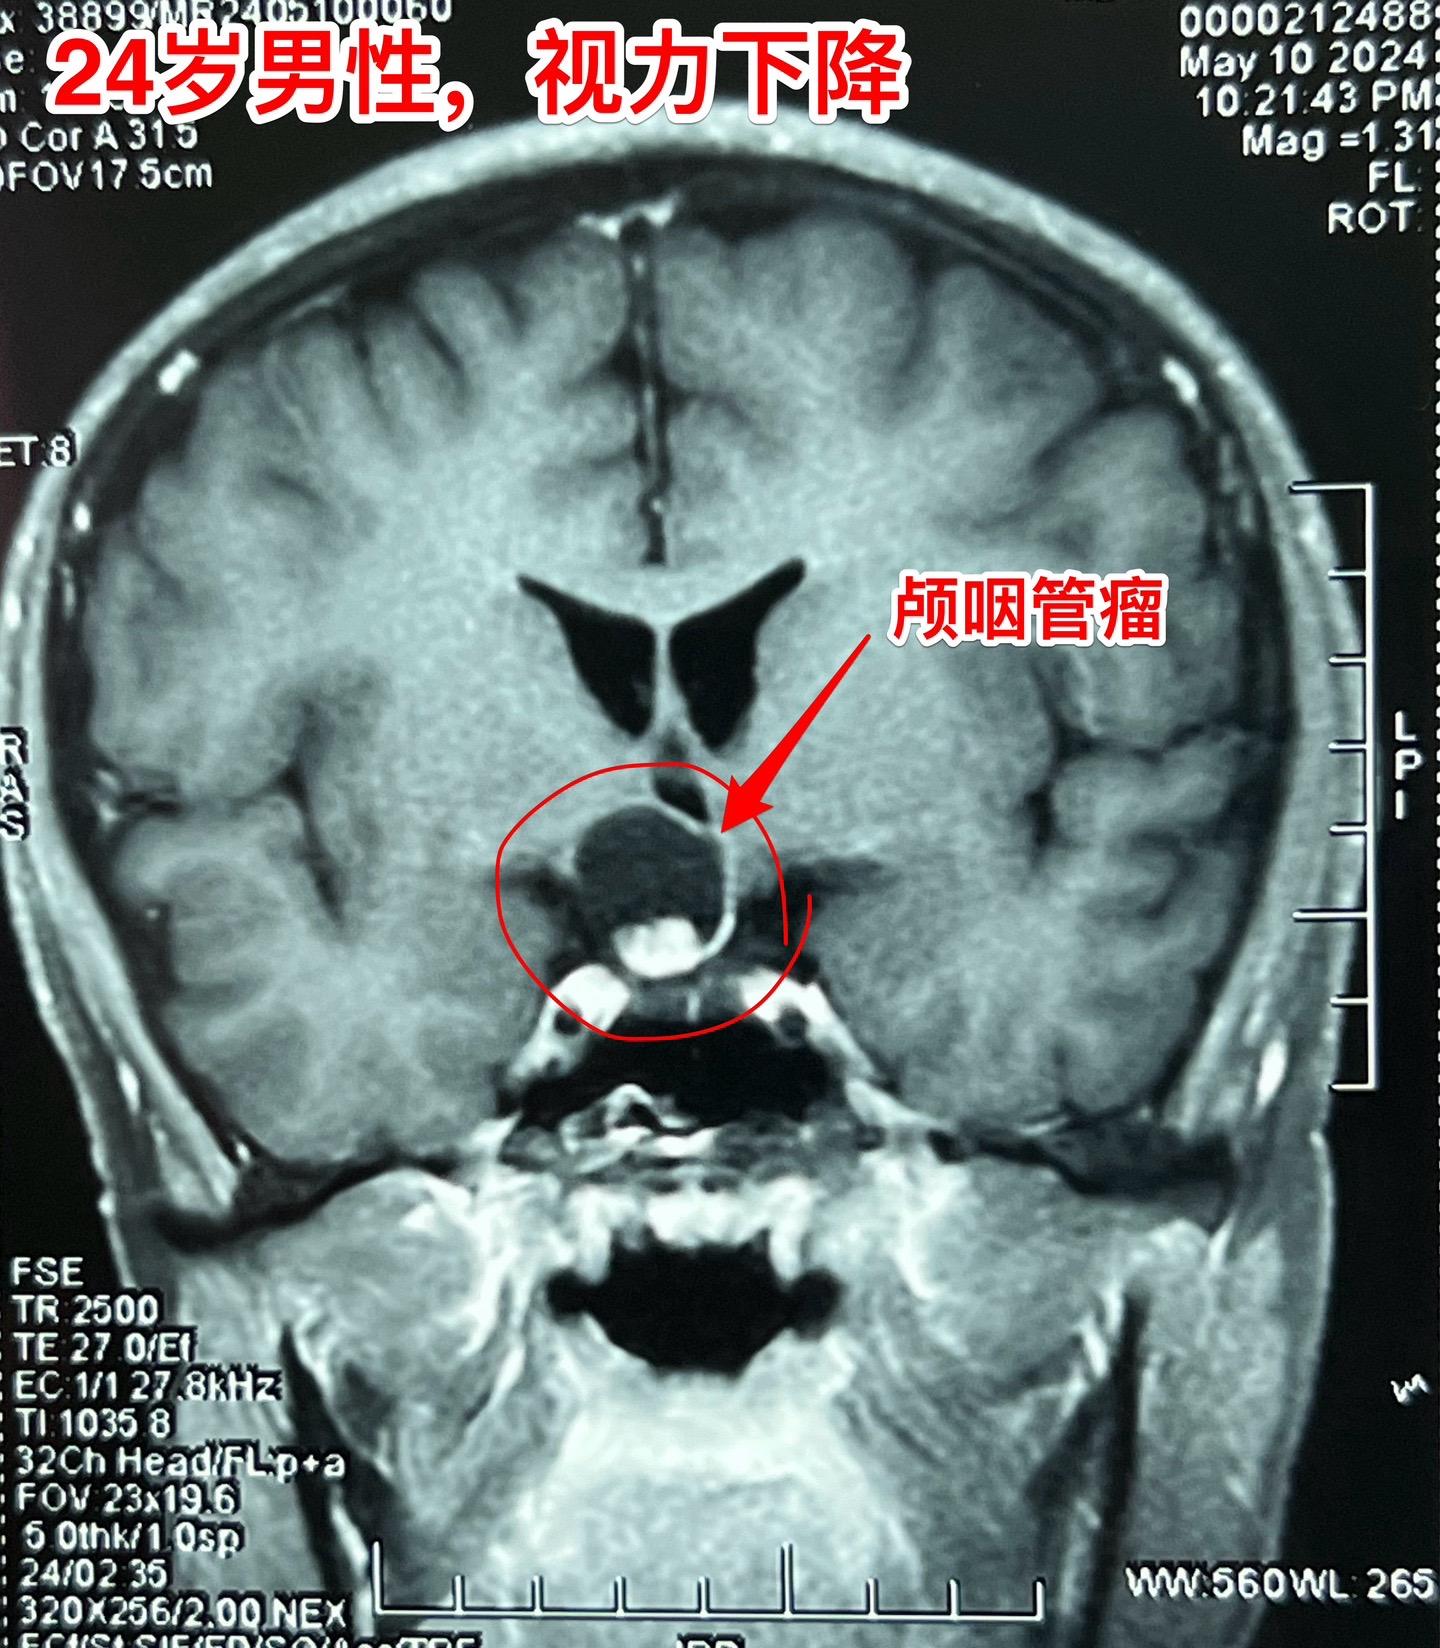

5月17日两例颅咽管瘤手术。第一例患者56岁,双眼视力都很差了,之前做过两次开颅手术,为乳头型颅咽管瘤复发。 第二例患者,24岁男性,因视力下降发现颅咽管瘤,也是乳头型颅咽管瘤。 两例患者手术入路不同,效果都满意,颅咽管瘤均得到完全切除。希望肿瘤不复发。